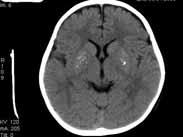

• 耳源性腦膿腫

耳源性腦膿腫為化膿性中耳乳突炎所并發的腦組織內的膿液積聚。占腦膿腫發病率的80%。是一嚴重、危險的并發癥。多見于青壯年。膿腫多位于大腦顳葉及小腦。多由于膽脂瘤型中...